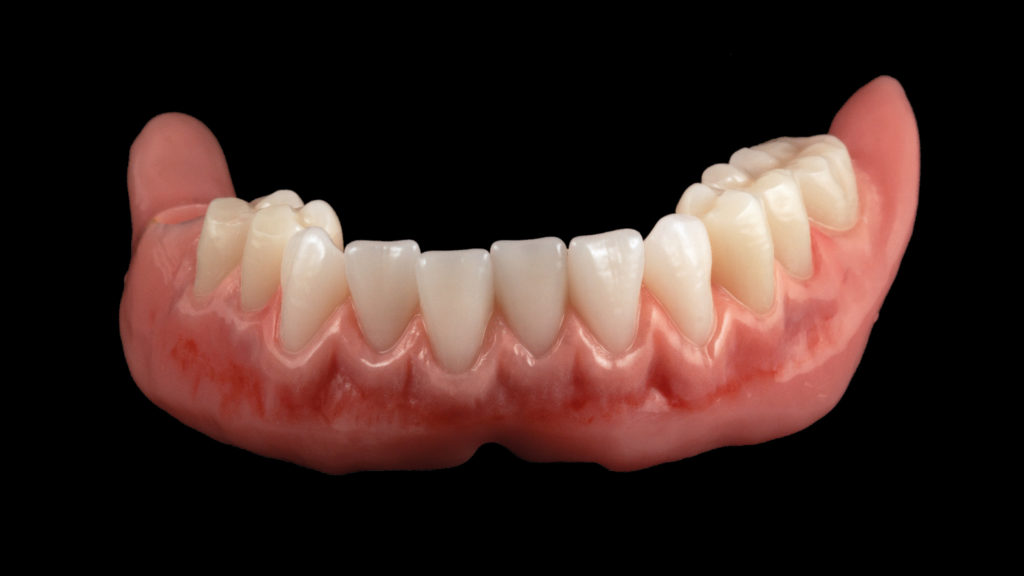

Ein Silikonschlüssel wurde von den Wachsaufstellungen hergestellt; die Zähne wurden entnommen, gereinigt und basal sowie zervikal für die Umsetzung in Kunststoff konditioniert (Abb. 12). Nach der Repositionierung der Konfektionszähne in den Silikonschlüssel wurden vor dem Ausgießen der kompletten Prothesenbasis mit dem Polymer Castdon das vestibuläre Lippenschild und der Gaumenbereich mit Farben aus dem Denture-Art-System individualisiert. Nach der Repositionierung der Meistermodelle in den Schlüssel und der Autopolymerisation wurden die beiden Prothesen mit einem rotierenden Instrument ausgearbeitet. Die abschließende Politur erfolgte mit Bimsstein, Polierpaste und Polierrad. Je nach Patientenalter kann das Zahnalter durch eine mehr oder weniger starke Reduzierung der Oberflächentextur mit einer kurzen Politur gesteuert werden. In diesem Fall wurde die Oberflächentextur der Zähne konsequent durch die Verwendung eines Handstücks ausgespart, um die jüngere Wirkung der Konfektionszähne zu erhalten (Abb. 13 und 14).

Der Fall zeigt, dass mit den richtigen Konfektionszähnen nach dem ästhetischen Regelwerk und Freude an der zahntechnischen Kunstfertigkeit totalprothetische Rehabilitationen entstehen können, die den Vergleich mit aufwendigen keramischen Ganzkieferversorgungen nicht scheuen müssen (Abb. 15). Die Patientin war von dem hochästhetischen Ergebnis und dem stabilen Sitz ihrer neuen Prothesen begeistert und zeigte unmittelbar nach der Eingliederung ein neues Selbstbewusstsein. Die Konfektionszähne zeigten ein lebendiges Lichtspiel und gaben der Patienten ihr altersgerechtes Aussehen zurück (Abb. 16 bis 18).